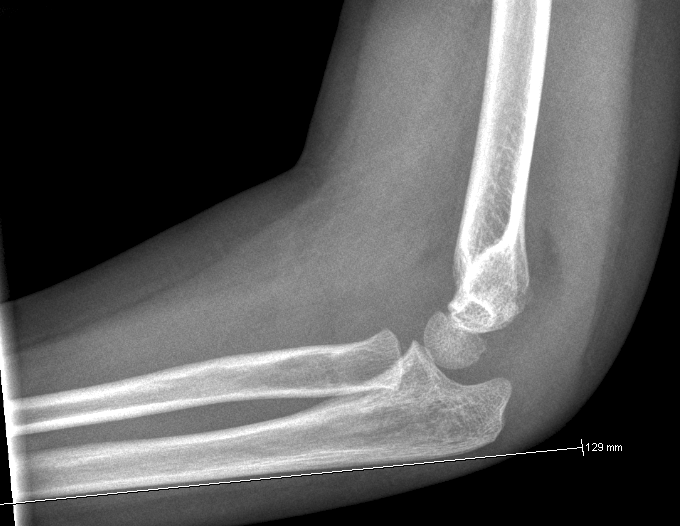

Dislokation: En linie langs forsiden af humerus går normalt igennem midterste

1/3 del af capitulum humeri. Hvis hele capitulum ligger bagved denne linje skal

der reponeres og osteosynteres i GA. Hos børn under 4 år tillades lidt større

Husk at vurdere at caput radii er på plads, ved at

kontrollere at en linje gennem radius går gennem centrum af capitulum humeri: